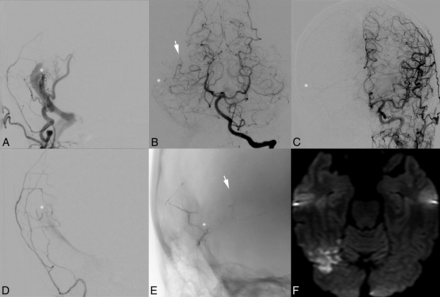

Postembolization infarction due to Onyx migration into a pial artery. A middle-aged woman with severe pulsatile tinnitus underwent endovascular therapy for a right transverse-sigmoid sinus junction Borden-Shucart grade I DAVF supplied principally by the middle meningeal and occipital arteries (A) and secondarily by the ipsilateral middle temporal artery (B) and tentorial branches from the contralateral middle meningeal artery (C). The fistula site is designated by a white asterisk. The fusiform gyrus branch of the middle temporal artery is indicated by a white arrow. Superselective injection of the right middle meningeal artery demonstrates the fistula site before embolization (D). Midembolization x-ray (E) demonstrates Onyx in the middle meningeal artery, fistula site, and refluxed into the pial fusiform gyrus branch of the middle temporal artery. The extent of reflux had not been evident on real-time intraprocedural blank roadmap imaging. DWI later the same day (F) demonstrates a fusiform gyrus infarction.